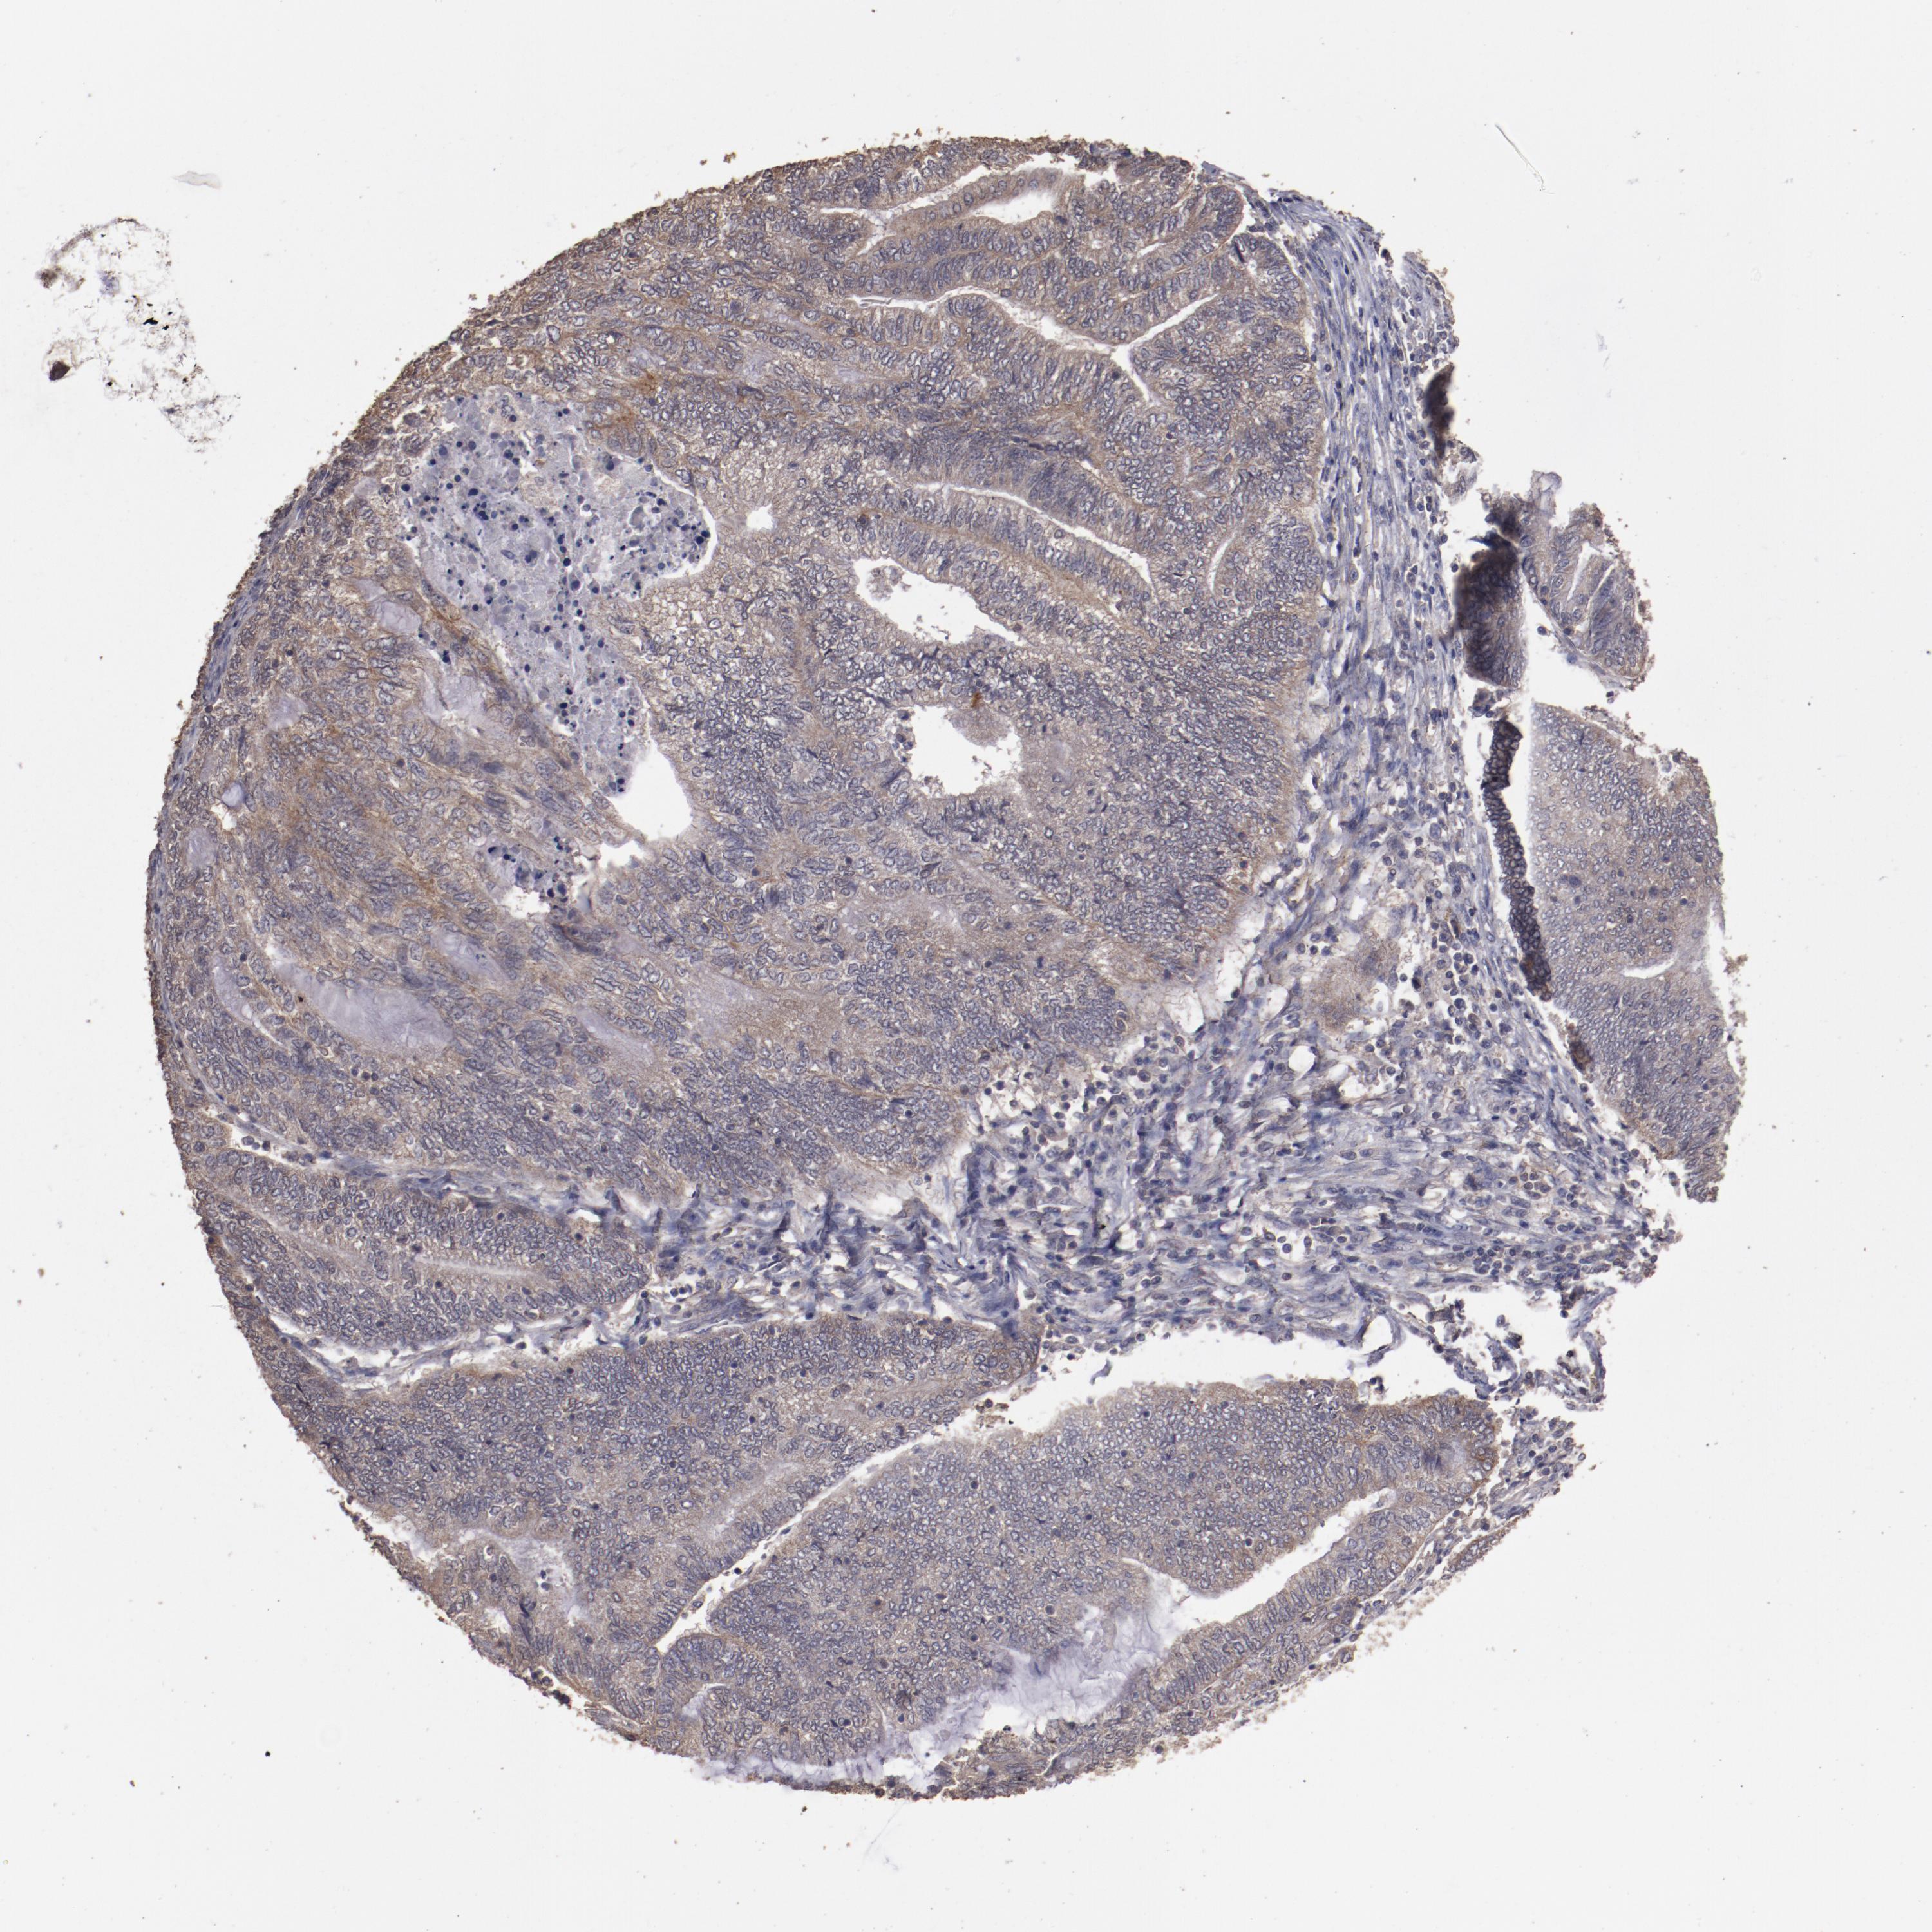

ENDOMETRIAL CANCER - Protein expressioni

A mouse-over function shows sample information and annotation data. Click on an image to view it in a full screen mode. Samples can be filtered based on level of antibody staining by selecting one or several of the following categories: high, medium, low and not detected. The assay and annotation is described here.

Note that samples used for immunohistochemistry by the Human Protein Atlas do not correspond to samples in the TCGA dataset.

Antibody stainingi

Antibody staining in the annotated cell types in the current human tissue is reported as not detected, low, medium, or high, based on conventional immunohistochemistry profiling in selected tissues. This score is based on the combination of the staining intensity and fraction of stained cells.

Each image is clickable and will lead to virtual microscopy that enables deeper exploration of all samples and also displays staining intensity scores, fraction scores and subcellular localization as well as patient and tissue information for each sample.

Antibody HPA001869

Antibody HPA023882

Staining

High

Medium

Low

Not detected

Intensity

Strong

Moderate

Weak

Negative

Quantity

>75%

75%-25%

<25%

None

Location

Nuclear

Cytoplasmic/membranous

Cytoplasmic/membranous,nuclear

Adenocarcinoma, NOS

Neoplasm, malignant, NOS

Adenoma, NOS